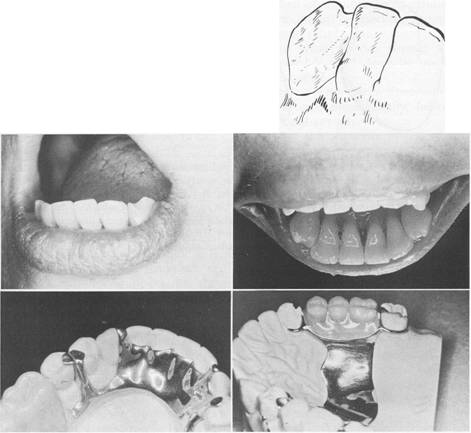

Fig. 6-23 A and B, Composite cingulum rest formed on mandibular canine. C, Sapphire ceramic ortho­dontic bracket bonded to lingual surface of mandibu­lar canine and shaped as lingual rest seat. (A and B courtesy Dr. Walter Homayoon, Long Island, NY; C courtesy Dr. Gustavo Tapia, Toluca, Mexico.)

Fig. 6-24 A and B, Incisal rest seat placed in mesial incisal edge of lower canine. Note that contact point is not involved in preparation of rest seat to support linguoplate (as seen in C). D, Distal incisal rest on canine furnishes excellent vertical support for tooth-supported removable partial denture and is not esthetically objectionable.

Fig. 6-26 Three views of incisal rest seat preparation on mandibular canine adjacent to a

modification space. Labial view demonstrates inclination of floor of rest seat, which allows forces to be directed along the long axis of tooth as nearly as possible. Note that floor of rest seat has been extended slightly onto labial aspect of tooth. As seen from a proximal view, proximal edge of rest seat is rounded rather than straight. Lingual view shows that all borders of rest seat are rounded to avoid sharp line angles. It is especially important to avoid a line angle at junction of axial wall of preparation and floor of rest seat. The rest that occupies such a preparation should be able to move slightly in a lateral direction to avoid torquing the abutment tooth.

Fig. 6-28 Labial view of configuration and 19cation of incisal rests on mandibular incisors and right canine.